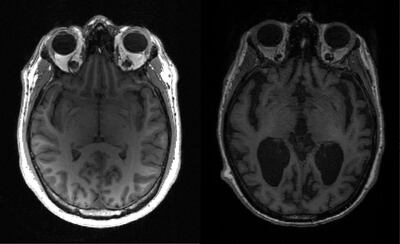

Imaging techniques found the vaccine and the antibody restored the function of nerve cells, increased glucose metabolism in the brain, restored memory loss and reduced the formation of amyloid beta plaques.